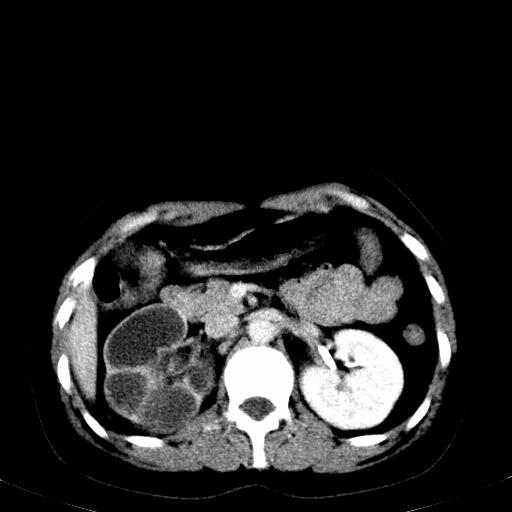

患者体检发现右肾体积增大,怀疑右肾积水

右肾多发囊肿,左肾、左输尿管结石

右肾重度积水,以肾盏积水明显,有分隔,上段输尿管轻度扩张,管壁增厚,考虑肾结核可能,请结合尿检查,胸部拍片排除肺结核。

右侧肾积水、左侧肾结石

右侧肾积水、左侧肾结石  ,要排除右肾结核可能。

右肾重度积水,建议ct向下扫描或逆行造影,左肾及左输尿管结石 .

患者尿常规正常,b超未发现明显结石,自身也无明显感觉异常。

请问多囊肾与肾积水怎么鉴别